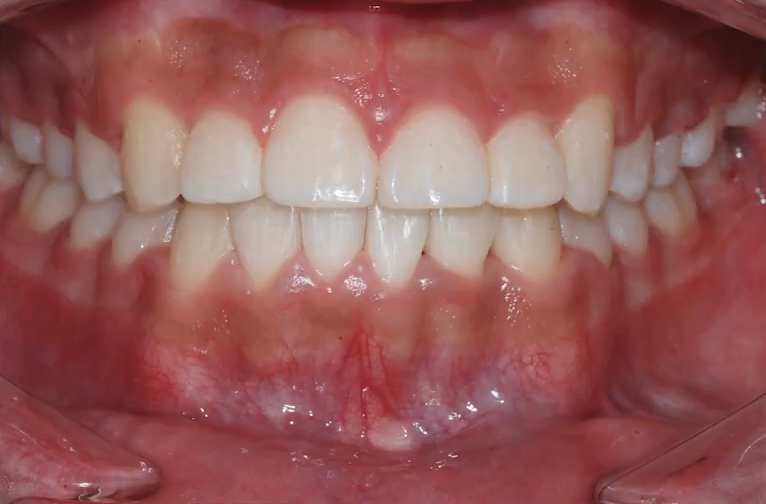

악궁확장 장치로 위, 아래 아치를 넓혀 자연스럽게 치아 사이를 벌려주고

그런 이후에 교정 장치를 부착해서 치아 배열을 고르게 해줬습니다.

덧니가 꽤 심했지만 확장을 통해 충분히 공간을 만든 후,

비발치로 교정을 끝낸 사례죠.

*치료 기간: 2022.03~2023.9

*치료 전후 사진은 환자의 동의하에 게재하였으며 별도 보정 없는 원본입니다.